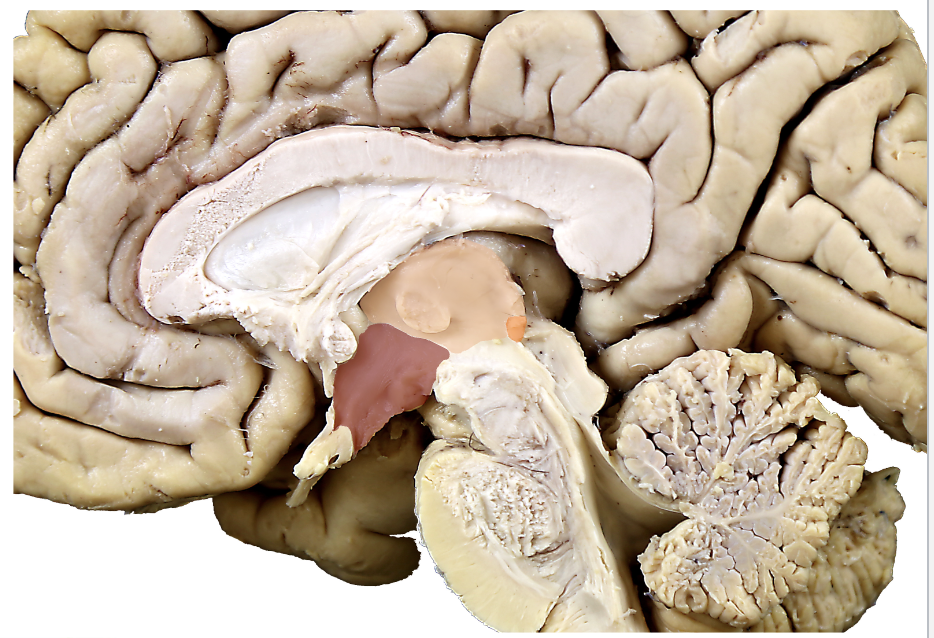

what structure is in orange?

epithalamus (pineal gland and habenula)

what structure is in red?

hypothalamus

what structure is in pink?

thalamus